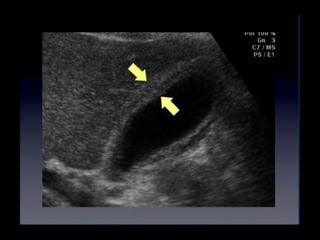

• Dilatación del coledoco

• Puede ser dificil de hallar

• Rotar al paciente para el lado izquierdo

• El transductor perpendicular al borde

costal

• Superior a la vena porta

Colecistitis

• Coledoco

• Promedio de diametro interno es de 4-6mm

• Mayor a 7mm es anormal

• CBD >1cm es indicativo de obstruccion

• Ver litos en el coledoco

• En pacientes colecistectomizados hasta 10 mm

puede ser normal